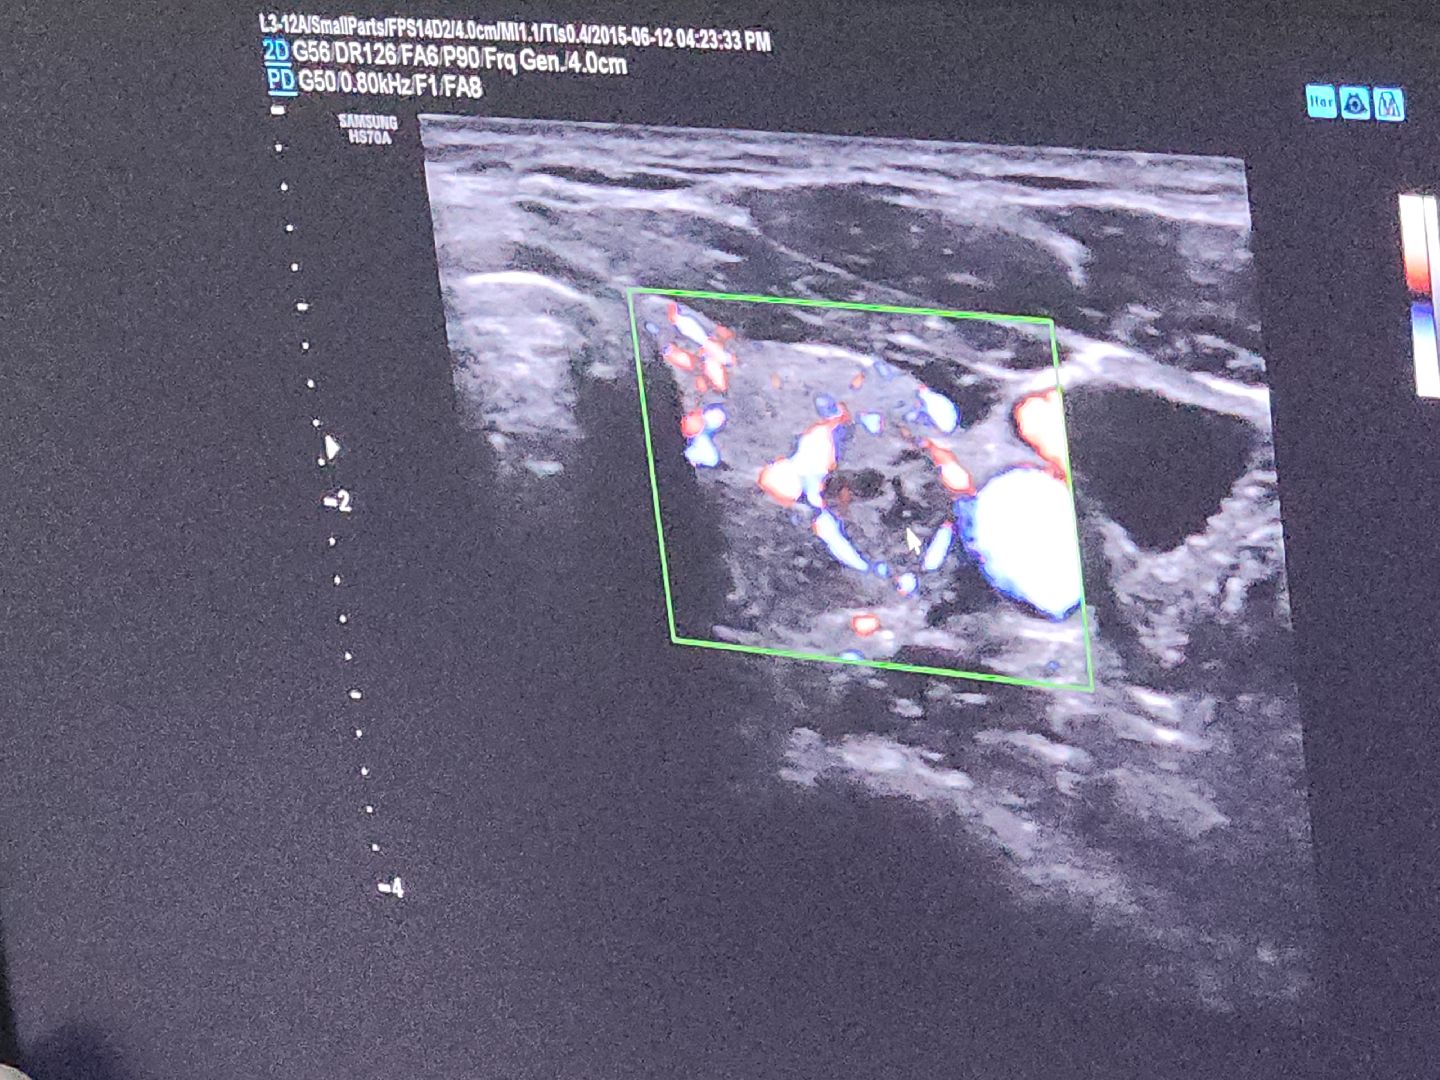

Мужчины могли сдать кровь на простатический специфический антиген (ПСА), помогающий раннему выявлению рака предстательной железы. Женщины – пройти УЗИ молочных желёз, выявляющее новообразования. Кроме того, каждый мог сдать анализ кала на скрытую кровь в целях выявления риска развития колоректального рака, рентген грудной клетки (скриннинг рака лёгкого), а также пройти консультацию онколога.